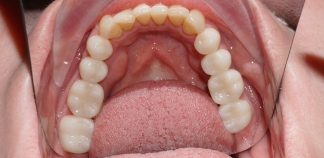

До лечения

Жалобы на то, что не может нормально жевать и улыбаться.

Пациенту 45 лет.

Как лечили

Проведена профессиональная гигиена зубов. Сняты старые коронки и мосты, пролечен кариес. Были установлены 9 имплантов. На верхние фронтальные зубы установлены цельноциркониевые коронки.

Лечение проведено в течение шести месяцев.

Лечащие врачи

МАРКОСЯН Геворк Сандроевич, ХОМУТОВА Татьяна Александровна, ТИГРАНЯН Варангюл Гургенович